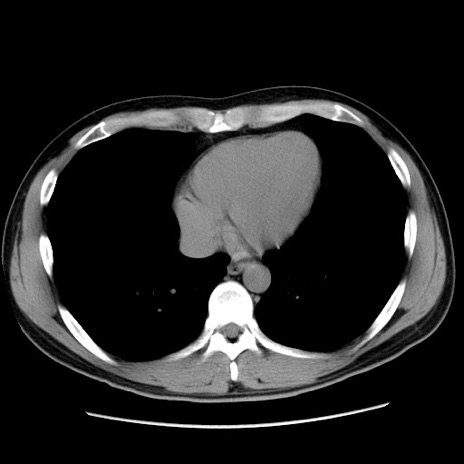

症例36(横断像)

【症例】20歳代 男性

【主訴】心窩部痛

【現病歴】今朝より上腹部痛あり。一旦軽快していたが再度出現したため救急要請。昨日夕に白身の魚を含む刺身を食べた。

【身体所見】BP 136/89mmHg、HR 74/min、BT 37.0℃、腹部:膨満、軟、心窩部に圧痛あり。反跳痛なし、筋性防御なし、腸雑音やや亢進あり。

【データ】WBC 17700、CRP 0.48